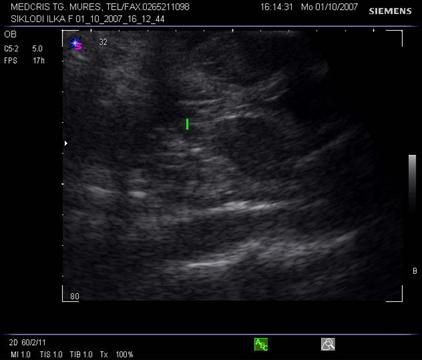

Fig. nr. 179. Planul 3 de sectiune a cordului evidentiaza plecarea trunchiului pulmonarei ( sageata ) din ventricului drept